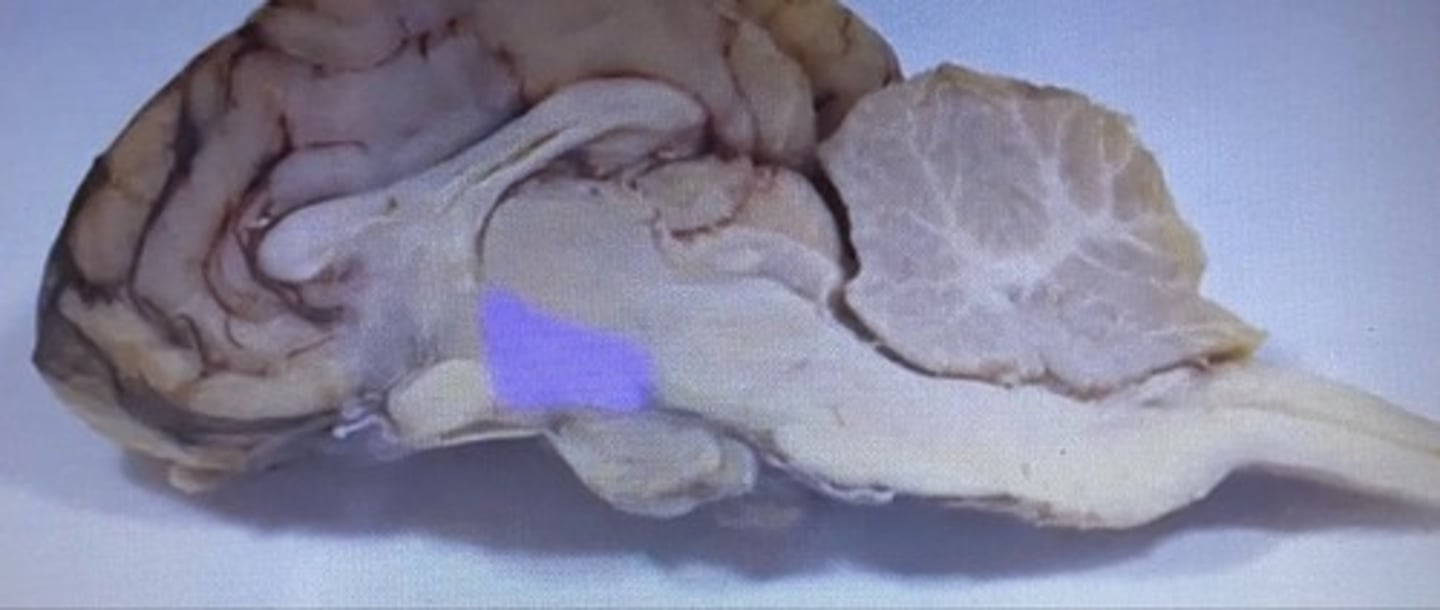

Sheep Pons

Pons

-bridge that links medulla oblongata to thalamus

sheep 4th ventricle